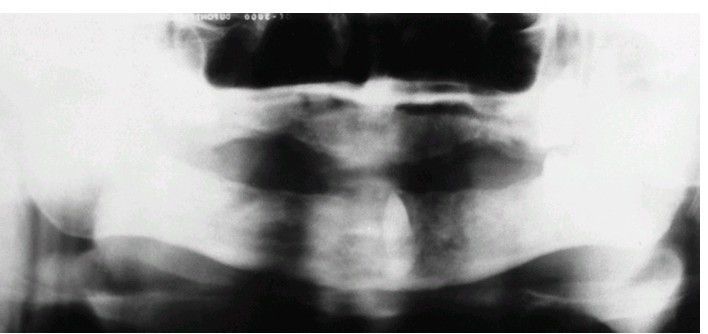

Impacted tooth under prosthesis

Impacted canine retained under a denture. The tooth is now at the surface and is causing infection.